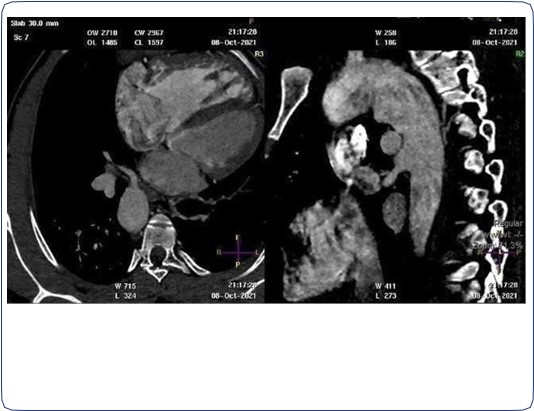

CT angiogram of chest shows complex cardiac disease including right-sided aortic arch (Figure 1), ventricular septal defect and overriding aorta (Figure 2). Non-visualization of the pulmonary trunk (Figure 3).

Figure 1: Contrast-enhanced axial CT chest at the level of the aortic arch showing right sided aortic arch.

Figure 2: Contrast-enhanced reconstructed 3 chambers view of the heart showing a ventricular septal defect and overriding aorta.